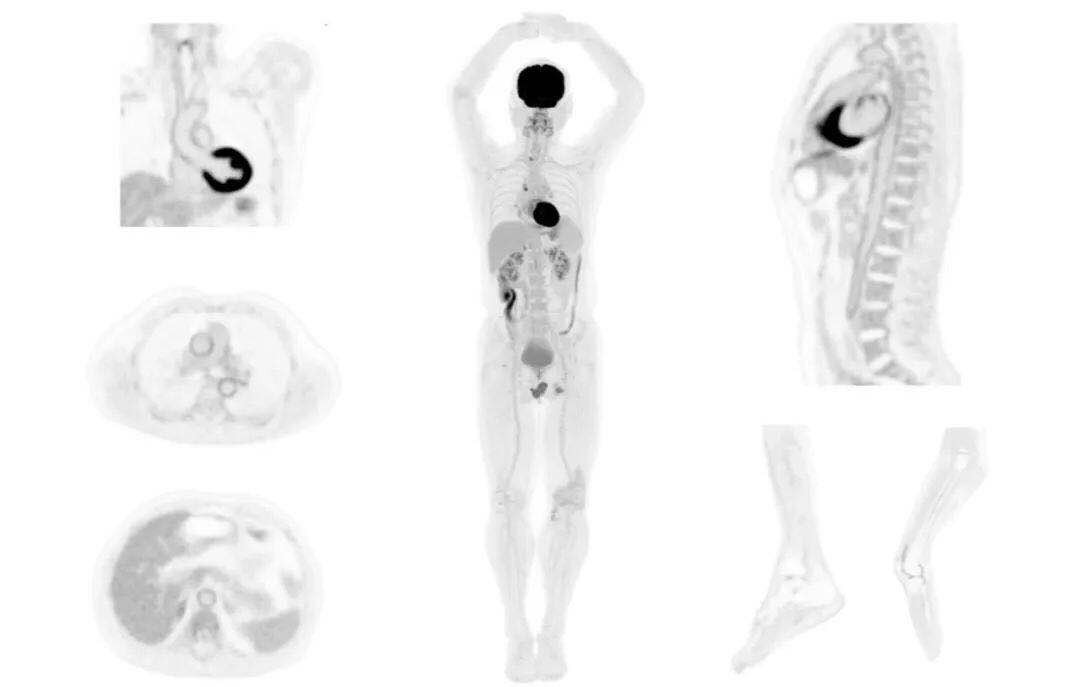

uExplorer探索者不再局限于傳統(tǒng)靜態(tài)代謝過程3D成像,而是在此基礎(chǔ)上新增一個(gè)維度——時(shí)間,從而實(shí)現(xiàn)4D全景成像。

注射總劑量為7.8mCi,14分鐘全身采集時(shí)間,在擁有超高靈敏度與超高分辨率的uEXPLORER上,即可得到展示顯示人體諸多精細(xì)結(jié)構(gòu)的高清三維圖像。

注射總劑量為7.8mCi,注射后1.6小時(shí),基于uEXPLORER探索者掃描1分鐘的圖像

注射總劑量為0.67 mCi FDG(低于常規(guī)劑量的十分之一),基于uEXPLORER探索者掃描15分鐘的圖像

注射總劑量為6.9mCi,注射后10小時(shí),基于uEXPLORER探索者掃描14分鐘的圖像